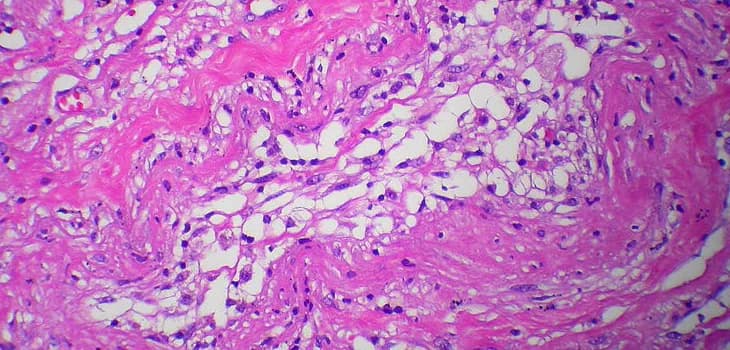

Die orthopädische Lipogems®-Behandlung nutzt das körpereigene Fettgewebe zur Behandlung verschiedener muskuloskelettaler Probleme. Dieses minimalinvasive Verfahren nutzt die regenerativen Eigenschaften von Fettzellen zur Förderung der Heilung und Schmerzreduktion in Gelenken, Sehnen und Knochen. Die Behandlung bietet eine natürliche Alternative für Patienten, die Mobilität und Lebensqualität verbessern möchten, ohne auf größere Operationen zurückgreifen zu müssen.

Gelenkerkrankungen wie Arthrose schränken die Lebensqualität von Millionen Menschen ein. Die regenerative Medizin hat therapeutische Ansätze revolutioniert, und Lipogems hat sich als echter Game Changer etabliert und bietet eine wirksame Lösung, die Schmerzen reduziert, Mobilität verbessert, Entzündungen bekämpft und Geweberegeneration fördert.

Hunderte von Studien und wissenschaftlichen Publikationen haben gezeigt, dass die Behandlung mit Lipogems erhebliche Vorteile für Patienten mit Arthrose bietet und länger anhaltende Ergebnisse als traditionelle medikamentöse Therapien liefert. Die Kombination mit Arthroskopie hat auch über mehrere Jahre nach der Behandlung positive Effekte gezeigt und die Gelenkfunktion verbessert.

Lipogems hat sich bei der Behandlung von Knie-, Hüft-, Schulter- und Sprunggelenkarthrose sowie bei Tendinopathien, Knorpelläsionen, Daumengrundgelenkarthrose und Karpaltunnelsyndrom als wirksam erwiesen. Seine Fähigkeit, Entzündungen zu reduzieren und Geweberegeneration zu stimulieren, macht es zu einer der vielversprechendsten Lösungen für diejenigen, die eine nicht-invasive Alternative zur traditionellen Chirurgie suchen.

Was ist Lipogems? Lipogems ist eine innovative Technologie, die minimale Mengen an Fettgewebe in einem vollständig geschlossenen System verarbeitet. Das Gewebe...

Das Lipogems®-System, das 2010 von Prof. Tremolada patentiert wurde, ist eine von der FDA zugelassene fortschrittliche Technologie, die die Fettzellen des...